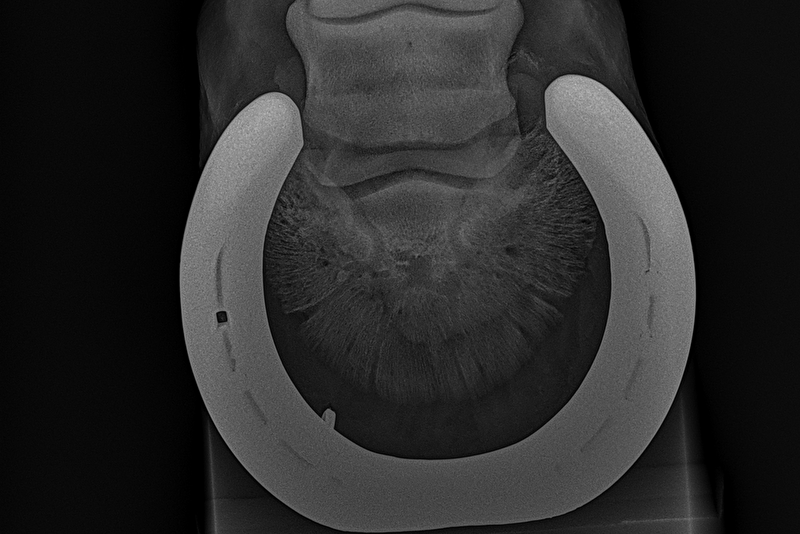

Insups schreef:Ik heb in 2022 een paard gekocht en volledig laten keuren. Die was door dierenarts 1 volledig in orde verklaard. Nu worden er nieuwe foto's gemaakt en blijkt hier toch een opmerking te zijn... Puur uit interesse ben ik benieuwd naar wat jullie zien